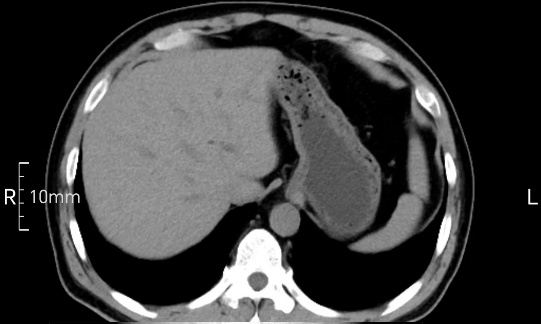

禁食但檢查前沒有喝飽,胃未能漲開,胃壁觀察效果不佳。